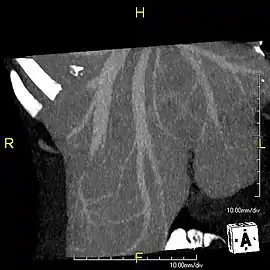

Maximum intensity projection (MIP) CT image as viewed anteriorly showing the anomalous hepatic veins coursing on the anterior surface of the liver

Lateral MIP view in the same patient as previous image